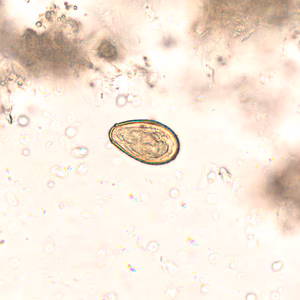

Eggs of Opisthorchis spp. in wet mounts.

Diagnosis is based on microscopic identification of eggs in stool specimens. However, the eggs of Opisthorchis are practically indistinguishable from those of Clonorchis. The adult fluke can also be recovered at surgery.